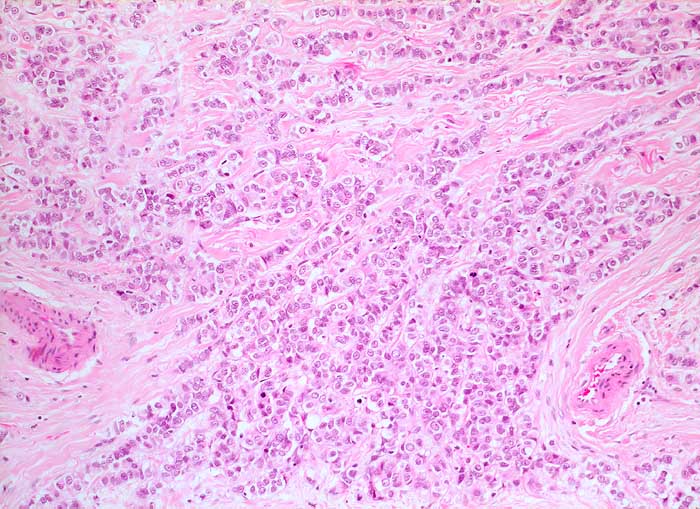

Lobuläre Mammakarzinome sind im Gegensatz zu den invasiv duktalen Karzinomen im Erguss viel weniger leicht erkennbar. Die Tumorzellen sind etwa so gross wie Mesothelien oder Makrophagen. Sie liegen einzeln oder in kleinen Gruppen und bilden zeilenförmige Verbände. Ihre Kerne sind hyperchromatisch, diskret entrundet oder gekerbt und auch von der Kernstruktur her kaum von Mesothelien oder Makrophagen unterscheidbar. Unten werden zwei verschiedene Fälle gezeigt. Der erste Fall zusätzlich mit histologischer Korrelation.